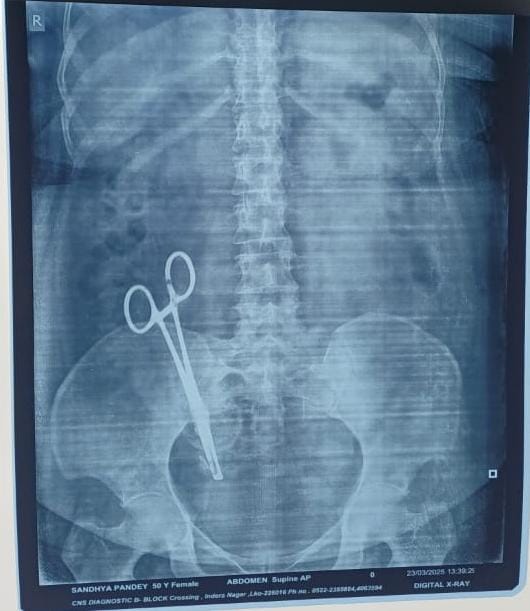

सर्जरी के दौरान पेट में छोड़ी कैची

17 साल बाद पता चलने पर सर्जरी कर निकाला गया

सलेमपुर नगर के इचौना पश्चिमी के मूल निवासी अरविंद पाण्डेय जो कि कोऑपरेटिव सोसाइटी पंचायत उपनिदेशक के पद पर कार्यरत है और लखनऊ के इन्दरा नगर में निवास करते है । इनकी पत्नी ने 26 फरवरी 2008 में लखनऊ के एक नामी नर्सिंग होम में सर्जरी से बच्चे को जन्म दिया ।इसके कुछ समय बाद से ही इनकी पत्नी के पेट में दर्द रहने लगा इस समस्या के इलाज के लिए अरविंद पाण्डेय ने अपनी पत्नी को उसी नर्सिंग होम के डॉक्टर से दिखाया जिसपर उनके द्वारा कुछ दवाएं देकर साधारण दर्द होना बताया और लंबे समय तक यह प्रक्रिया चलती रही और धीरे धीरे 17 साल बीत गए अब कुछ समय पूर्व अरविंद पाण्डेय ने परेशान हो कर डॉक्टरी सलाह पर अपनी पत्नी का एक्सरे कराया तो पेट में कैची होने का पता चला । फिर केजीएमयू के एक डॉक्टर से दिखाने पर उन्होंने दुबारा सर्जरी कर कैची निकलने की राय दी जिसपर सर्जरी कर कैची निकाली गई ।इस संदर्भ में अरविंद पाण्डेय ने लखनऊ के गाजीपुर थाने में तहरीर दी है ।